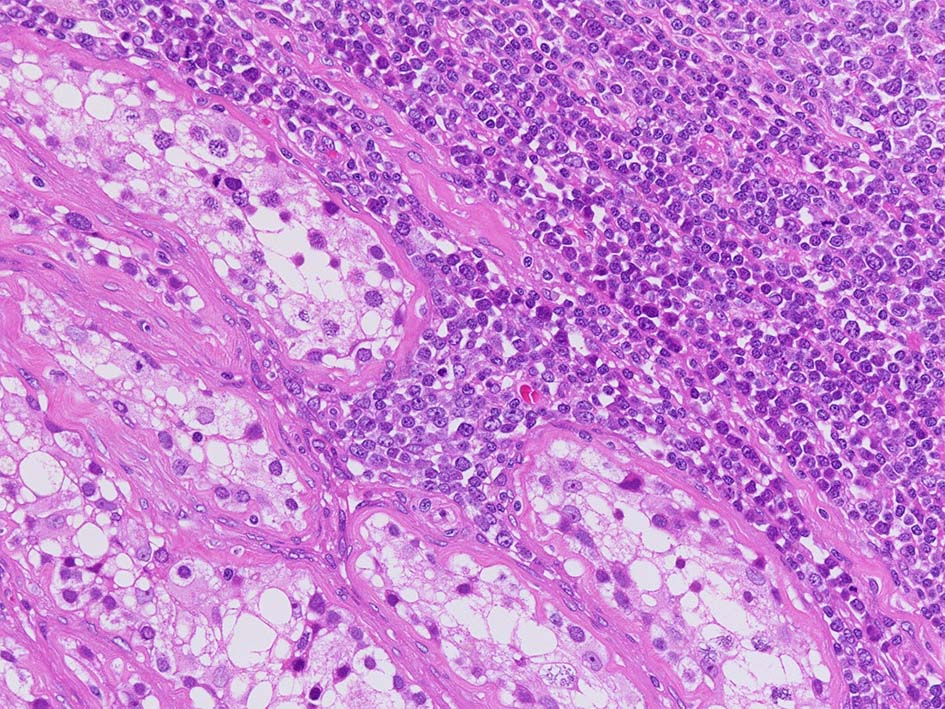

精細管の多くがスペアされ, 間質にlymphoid cellsが密に浸潤している. わずかな精細管に浸潤が認められ萎縮や破壊像が認められる. 精細管において Lymphoepithelial lesion(LEL)に似た所見がある.

類円形/多稜形の核をもつN/C比大の細胞. 粗大なクロマチンが増加, 核小体は不明瞭. DLBCLに認められるcentroblasts/ immunoblastsの細胞所見と異なる.